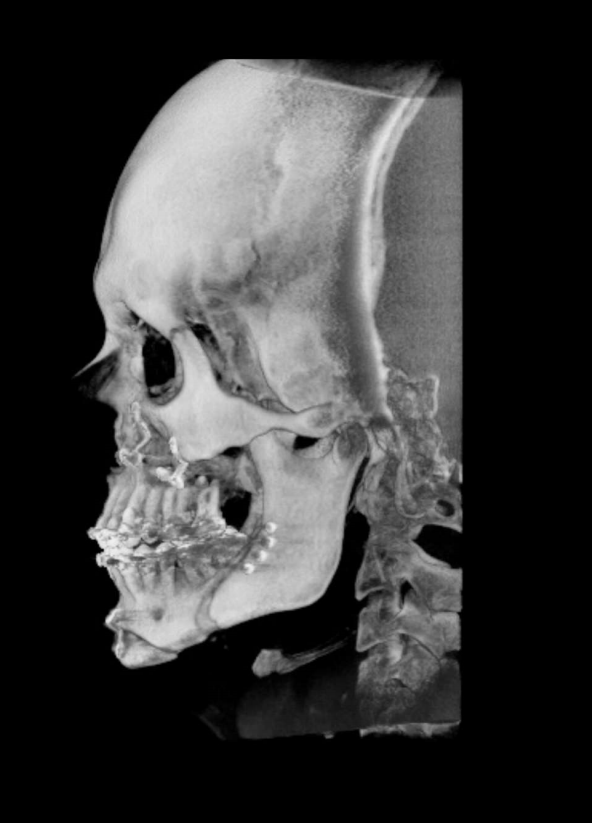

TC de face (do Hióide à Glabela), reconstrução 3D do tecido ósseo, radiografia panorâmica, telerradiografia lateral com traçado, cortes transversais e axial de maxila e mandíbula e arquivo DICOM- entregue em pasta de Pvc.

TC de face (do Hióide à Glabela), reconstrução 3D do tecido ósseo, radiografia panorâmica, telerradiografia lateral e frontal com traçado, cortes transversais e axial de maxila/mandíbula e arquivo DICOM – entregue em pasta de Pvc.

TC de face (do Hióide à Glabela), reconstruções 3D do tecido mole/ósseo/vias aéreas, radiografia panorâmica, telerradiografia lateral e frontal com traçado, cortes transversais e axial de maxila/mandíbula, ATM e arquivo DICOM – entregue em pasta e caixa de Pvc.